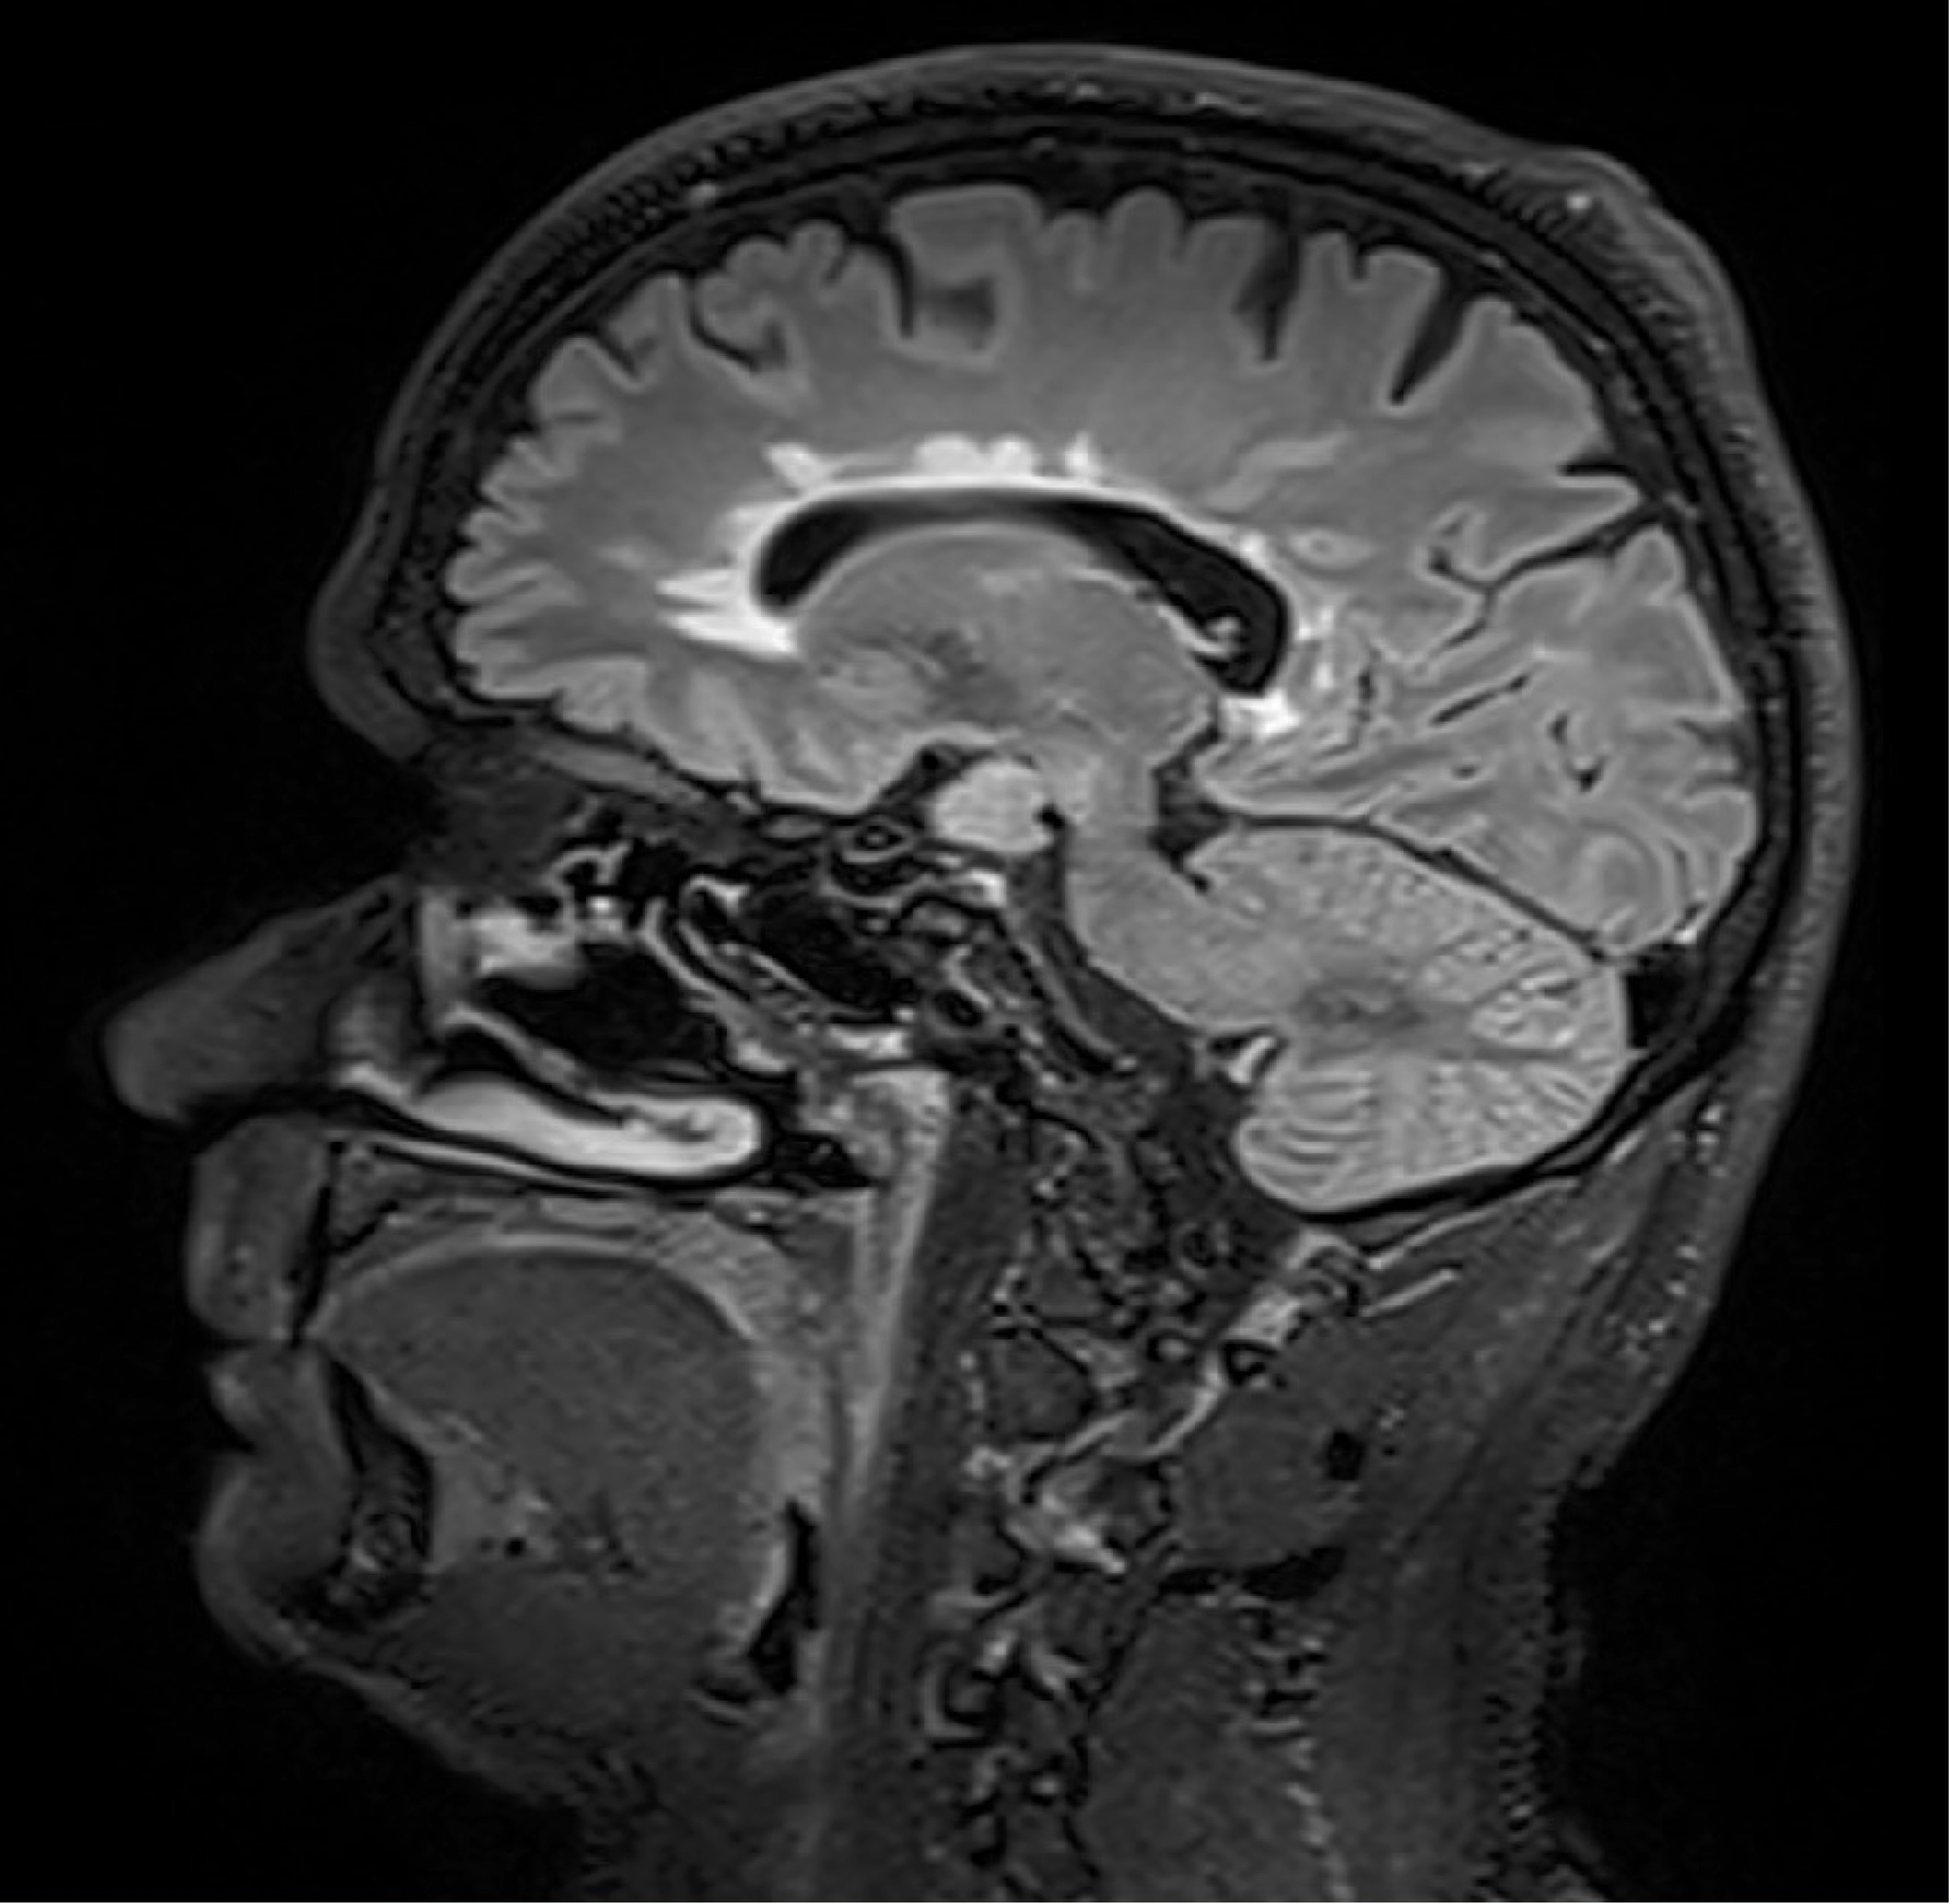

BU: Die Aufnahmen aus der Magnetresonanztomographie zeigen einen jungen Patienten mit Multipler Sklerose mit mehreren entzündlichen Läsionen des Gehirns. (© Radiologie Innsbruck)

Abseits klinischer Symptome, die von Einschränkungen des Sehvermögens bis hin zu Lähmungserscheinungen ein breites Spektrum umfassen, kann die Krankheitsaktivität bei MS auch bildgebend dargestellt werden. „Der Nachweis entzündlicher Läsionen im Gehirn mittels MRTerlaubt auch eine Einschätzung geringerer Krankheitsaktivität, denn vermeintlich stabile Patient:innen können trotz Therapie weiterhin neue, klinisch stumme, entzündliche Veränderungen entwickeln“, weiß Neuroimmunologe Harald Hegen, der an der Innsbrucker Univ.-Klinik für Neurologie bereits seit vielen Jahren zu MS forscht.

Die Ergebnisse einer neuen Multicenterstudie zu Multipler Sklerose könnten die Therapie dieser chronisch entzündlichen Erkrankung entscheidend verbessern. Forschende der Medizinischen Universitäten Innsbruck und Wien sowie des Inselspitals, Universitätsspital Bern belegen, dass zwei oder mehr in der Magnetresonanztomographie (MRT) sichtbare Läsionen im Gehirn innerhalb eines Jahres für eine Therapieintensivierung sprechen. Damit liegen erstmals eindeutige und evidenzbasierte Kriterien für eine Therapieanpassung vor.